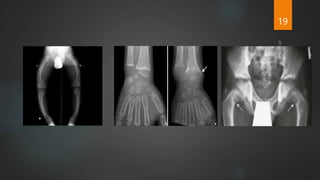

Radiological signs

 Generalized osteopenia

 Wide medullary canal and penciling of cortex

 Bowing deformity of long bones

 Widening of growth plate

 Cupping or flaring of metaphysis

 Looser’s zone (Milkmaids pseudofractures or Umbau zones)

 In severe rickets, margins of tarsal and carpal ossification center may disappear.

19

 In healing rickets

 Provisional line of calcification (white line)

 Recalcification of spongiosa in the metaphysis

 Dense line at the ends of metaphysis

 Epiphseal shadow defined

 End of shaft and epiphysis becomes clearly differentiated

 Finally, the bone appears to be normal